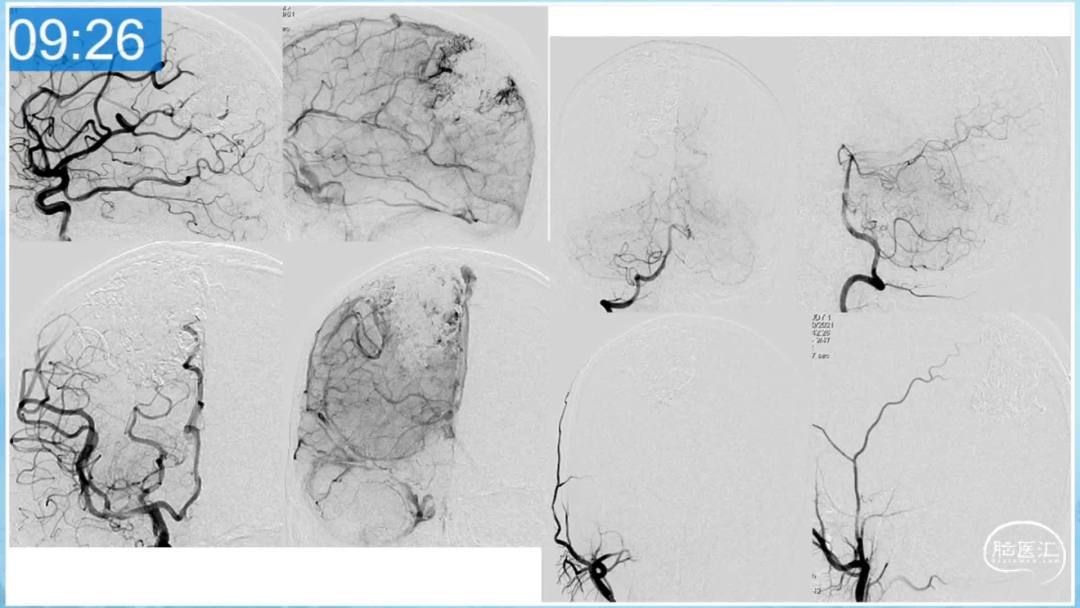

本期为大家特别分享:空军军医大学唐都医院邓剑平教授的精彩会议内容《颅内动静脉畸形的复合手术治疗》,欢迎大家阅读和分享!

合理的复合平台下的综合治疗,针对每一个病变对应不同方法安全性分析,不预设、不排斥,每种技术发挥到最佳,互相保障。